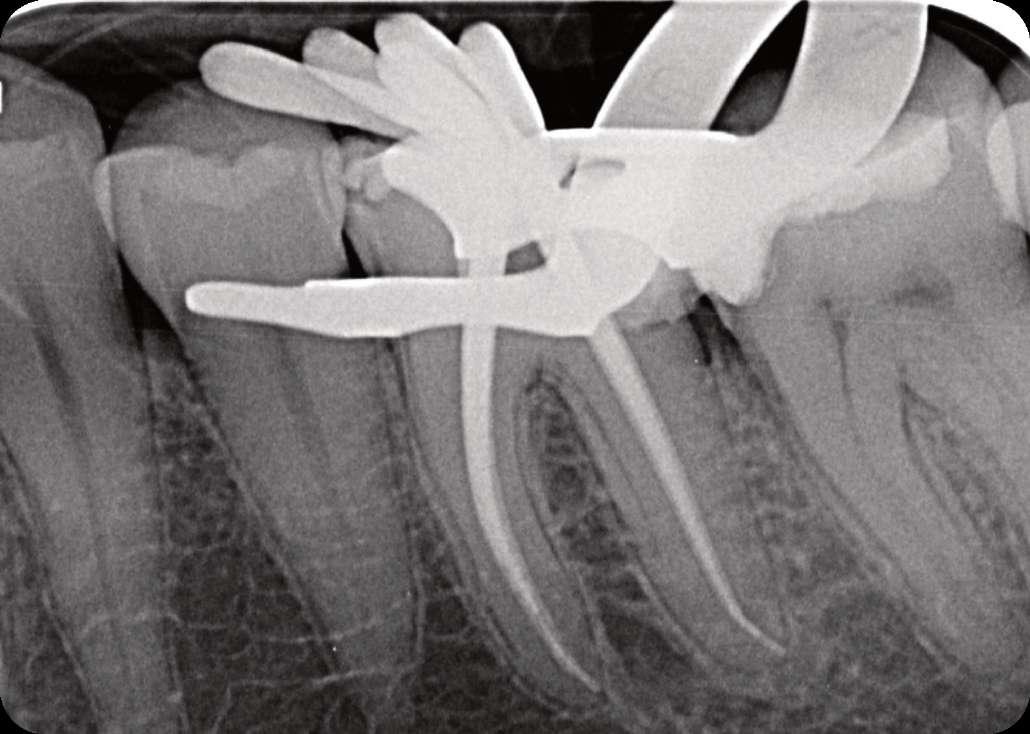

Präoperativ

Der erste untere, linke Backenzahn zeigt einen Zerfall auf dem distalen Teil mit dem Symptom einer irreversiblen Pulpitis. Zuerst wird der Karies entfernt und der Zahn wird mit einer temporären Füllung wieder aufgebaut. Danach wird der Kofferdam platziert und der Zugangshohlraum steht.

Vier Kanäle wurden mit dem SX EdgeTaper Platinum eröffnet. Auch der koronale Teil wurde mit dem S1 EdgeTaper Platinum erweitert. Arbeitslänge und Durchgängigkeit werden mit einer #10 K-Feile erreicht. Die A #15 K-Feile wurde verwendet, um Länge und Durchgängigkeit zu gewährleisten. Dank der Technologie von EdgeNedo war ich im Stande, die Feile für eine komfortable Formgebung vorzuformen, auch wenn die Öffnung reduziert wurde. S1, S2, F1 und F2 EdgeEndo Platin wurde bis zur gesamten Länge des Kanals eingebracht.

Während der Isthmus-Reinigung zeigte sich zwischen den mesialen Kanälen ein zusätzlicher Kanal. Die Formgebungsphase erfolgte schnell und effizient dank SX zum F2.

Das Röntgenbild zeigte eine große Länge und einen gemeinsamen Ausgang für zwei der drei mesialen Kanäle.

Die Wurzelfüllung erfolgte mit einer einzigen Kegeltechnik unter Verwendung des BUSA EndoSequence Bioceramic Sealer. Das Post-OP-Röntgen zeigt sehr hohe Dichte in der gesamten Länge der Wurzelfüllung.